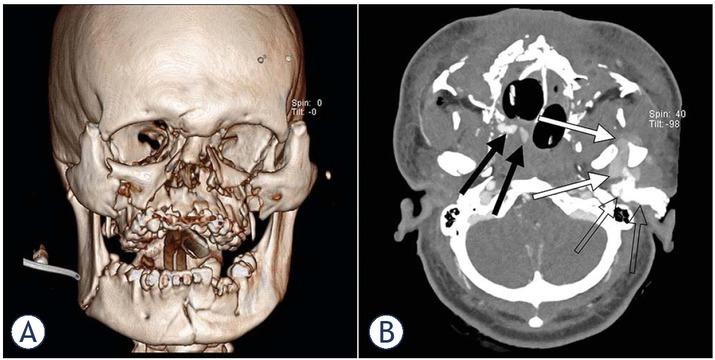

A 20-year-old, previously healthy male was brought to the emergency department in 2019 after an accidental 20 m (65 ft), head-first fall to the ground. He had been cleaning windows of his 7th floor dorm room when he lost balance and fell. Eyewitnesses reported the patient had been lying on his stomach after impacting the ground but later managed to roll on his back by himself. A physician-led emergency medical service arrived on the scene in 10 minutes, finding the patient verbally responsive and making an effort to get up. Initial Glasgow Coma Scale (GCS) was an estimated 13. Severe facial trauma compromising the airway and, within a few minutes, cessation of spontaneous respiration necessitated rapid sequence intubation which proved challenging with several failed attempts. Asystole was observed on ECG prompting resuscitation efforts that resulted in the return of spontaneous circulation and sinus rhythm 20 minutes later. Upon arrival at a Level I trauma centre, the patient presented with GCS 5, blood pressure 70/40 mmHg, heart rate 100/min., a multifragment facial fracture (Figure 2A), a ruptured right eye, massive bleeding from the nose and the left ear, a fractured right 4th rib, a fractured left radius, a displaced left femoral fracture and a fractured left tibia. Adhering to our institution’s standard trauma protocol, the possible abdominal and thoracic sources of major blood loss were excluded. Astonishingly, US, XR, CT and CTA imaging indicated no significant damage to the neurocranium, parenchymal organs or major thoracic or abdominal vessels. Aorto-cervical CTA was then performed, revealing contrast extravasation from the left IMA and the right sphenopalatine artery (SPA) (Figure 2B). This was consistent with the clinical presentation of severe antero-posterior epistaxis and pulsatile bleeding from the left ear. Nasal packing using balloon catheter inserted through the nares into the nasopharynx was performed by an ear, nose and throat (ENT) specialist to successfully control the nose bleeding. Tamponade of the left ear, however, proved to be inadequate with profound bleeding still persisting. Surgical treatment to control the haemorrhage by ligating the left ECA was decided against due to lesion inaccessibility caused by extensive soft tissue damage and swelling. Blood pressure remained low (60/40 mmHg) despite having hitherto administered a total of 5 litres of fluids, including blood transfusion. Tranexamic acid and vasopressors were also applied, to little avail. In these life-threatening circumstances, TAE of the bleeding origins was considered the only remaining option.

(A) A 3D CT reconstruction showing multiple maxillo-facial fractures. (B) An aortocervical CTA showing two small hematomas in the region of the right pterygopalatine fossa and nasal cavity (black arrows) and a cm 3 × 4 cm hematoma in the region of the left masticatory space and deep parotid space (white arrows). Also visible is a hyperdense material used in left ear tamponade (empty arrows).